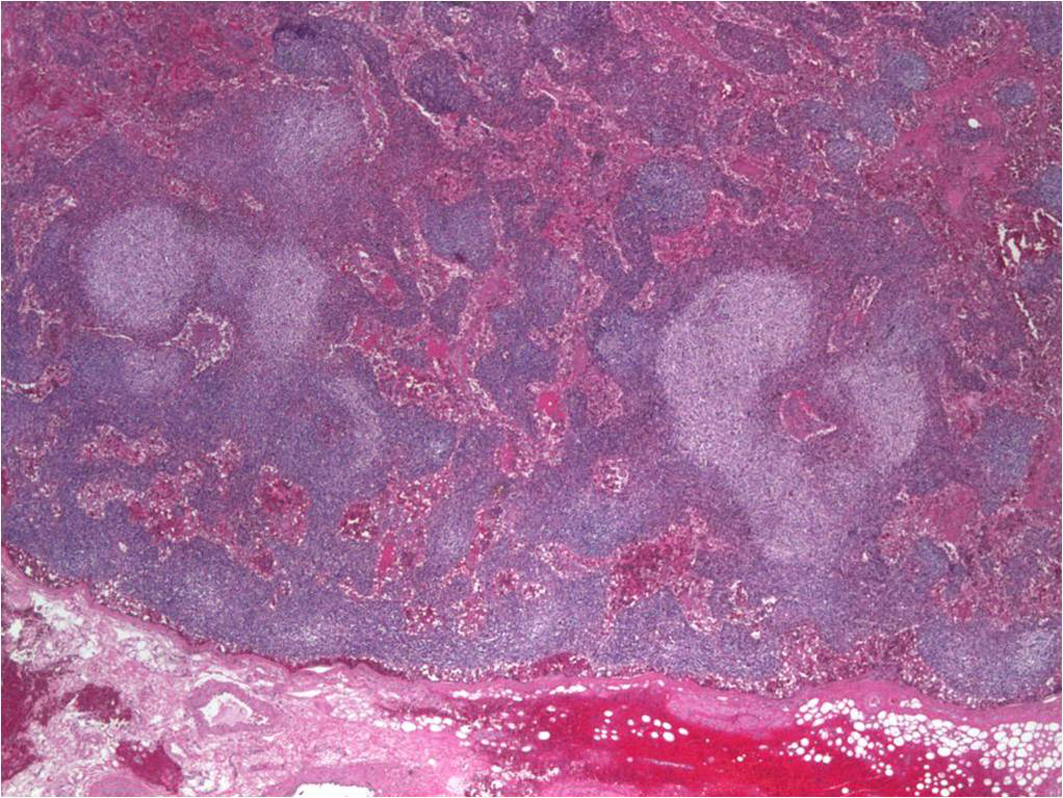

Serum electrophoresis revealed M spike with elevated IgG monoclonal protein with kappa light specificity. Urine also showed bence-jonce proteinuria with free kappa light chain. Beta 2 microglobulin levels were 32.5 mg/L. Cosyntropin stimulation test revealed primary adrenal insufficiency. Patient was started on IV hydration, dexamethasone and fludrocortisone. Patient’s electrolyte normalized on treatment and renal failure improved. Bone survey revealed lytic and blastic lesions in the vertebrae and other bones (Fig. 3). CT scan of chest also revealed large left 9th rib lesion with extra pleural mass effect. CT chest reconstruction revealed same blastic lesions in thoracolumbar vertebrae (Fig. 4). PSA, CEA and CA 19 - 9 levels were within normal limits and pelvic sonogram did not reveal any prostate nodule. HIV testing was negative and hepatitis testing revealed past infection with hepatitis B. Lymph node biopsy revealed reactive follicular hyperplasia with dermatopathic changes (Fig. 5). No other focus of malignancy was noted on CT chest, abdomen, pelvis and head. Before bone biopsy, patient’s condition deteriorated rapidly and developed DIC, GI bleed and retroperitoneal hematoma which lead to demise of the patient. Based on available data diagnosis of multiple myeloma with IgG kappa chain specificity was made.

![]() Click for large image | Figure 5. Axillary lymph node biopsy showing reactive follicular hyperplasia with dermatopathic changes. |

Our case does not meet criteria for POEMS syndrome - neuropathy which is critical as per Mayo clinic criteria for the diagnosis was absent in our case and our patient’s lymph node biopsy did not reveal Castleman’s disease. Our case has some unique presentations of multiple myeloma. Lymphadenopathy and osteoblastic lesions with IgG kappa chain predominance has never been described in literature with a case of multiple myeloma.